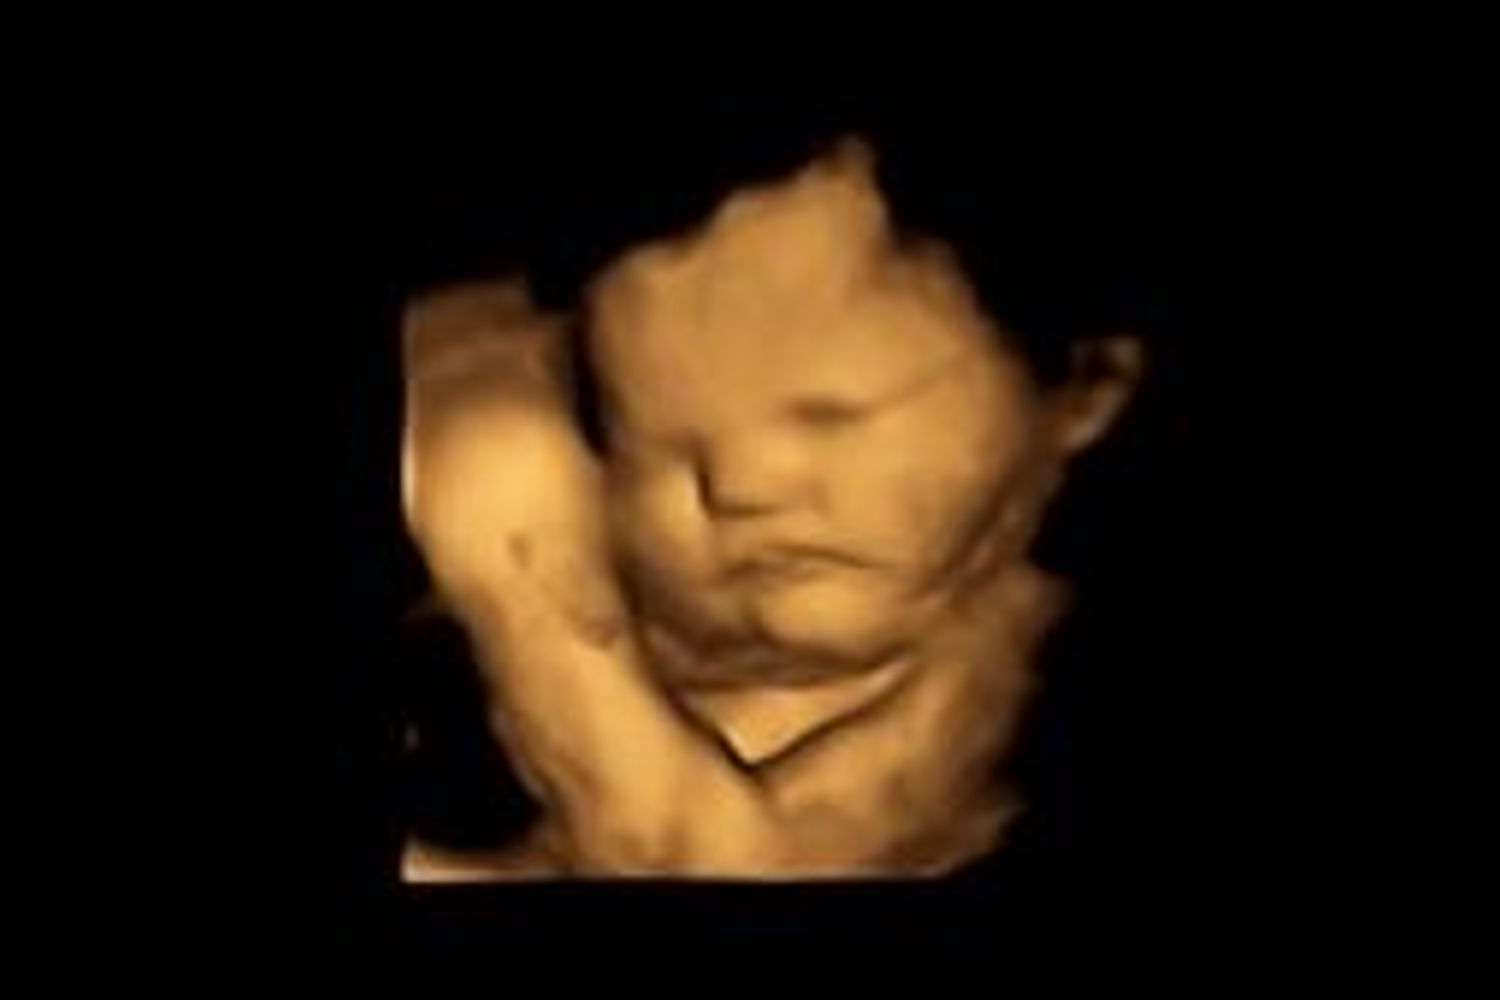

Gli esami hanno poi rivelato che la cinquantenne aveva un "bambino di pietra" - un feto calcificato - che le comprimeva l'intestino, risalente a un aborto spontaneo accaduto nove anni prima. Il feto, che ha le stesse dimensioni di una lattuga, aveva raggiunto 28 settimane di gestazione. La paziente ha però rifiutato l'intervento chirurgico, dicendo che credeva che le sue condizioni di salute fossero legate a un "incantesimo" che qualcuno le aveva lanciato in Africa.